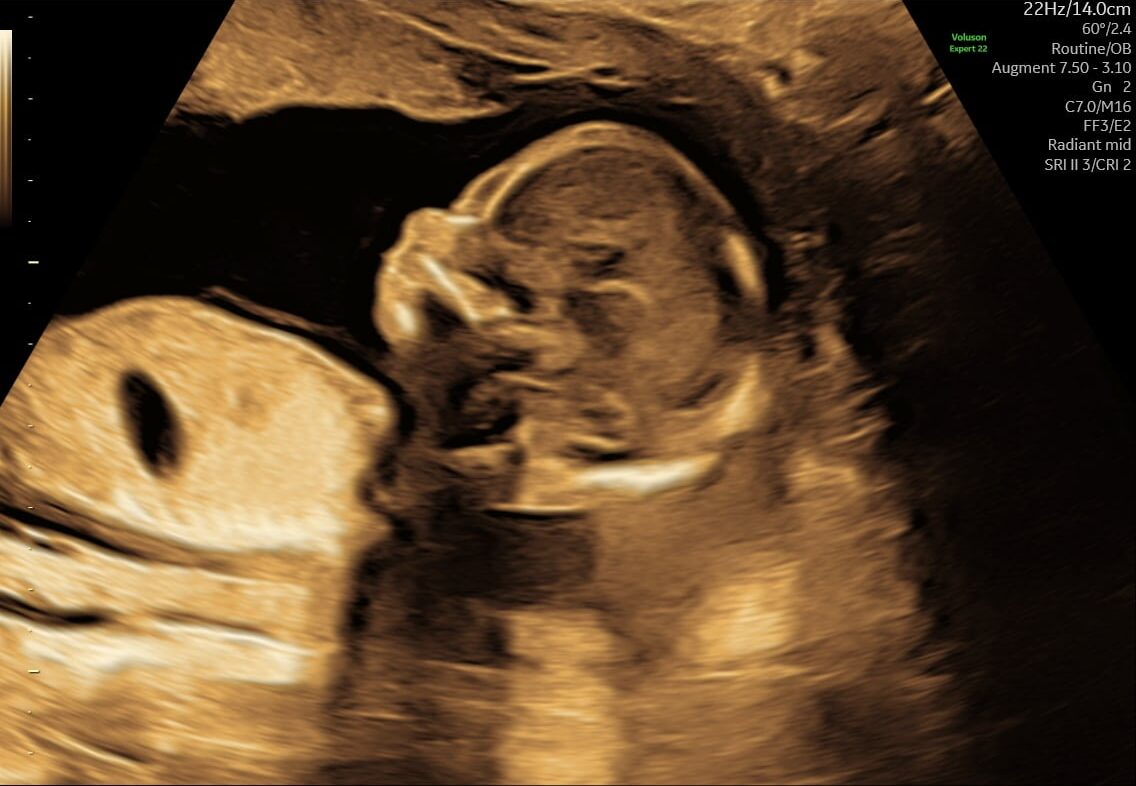

I uge 13 er fosteret omkring 7-8 cm langt og vejer cirka 23 gram. Fosteret begynder at se mere menneskeligt ud, og mange af de tidligere udviklinger fortsætter:

- Ansigtstræk: Øjnene og ørerne er nu tættere på deres endelige positioner. Øjenlågene er fuldt dannede og beskytter øjnene.

- Lemmer: Arme og ben er blevet længere og mere proportionale med kroppen. Fosteret kan begynde at sparke og bevæge sine små lemmer.